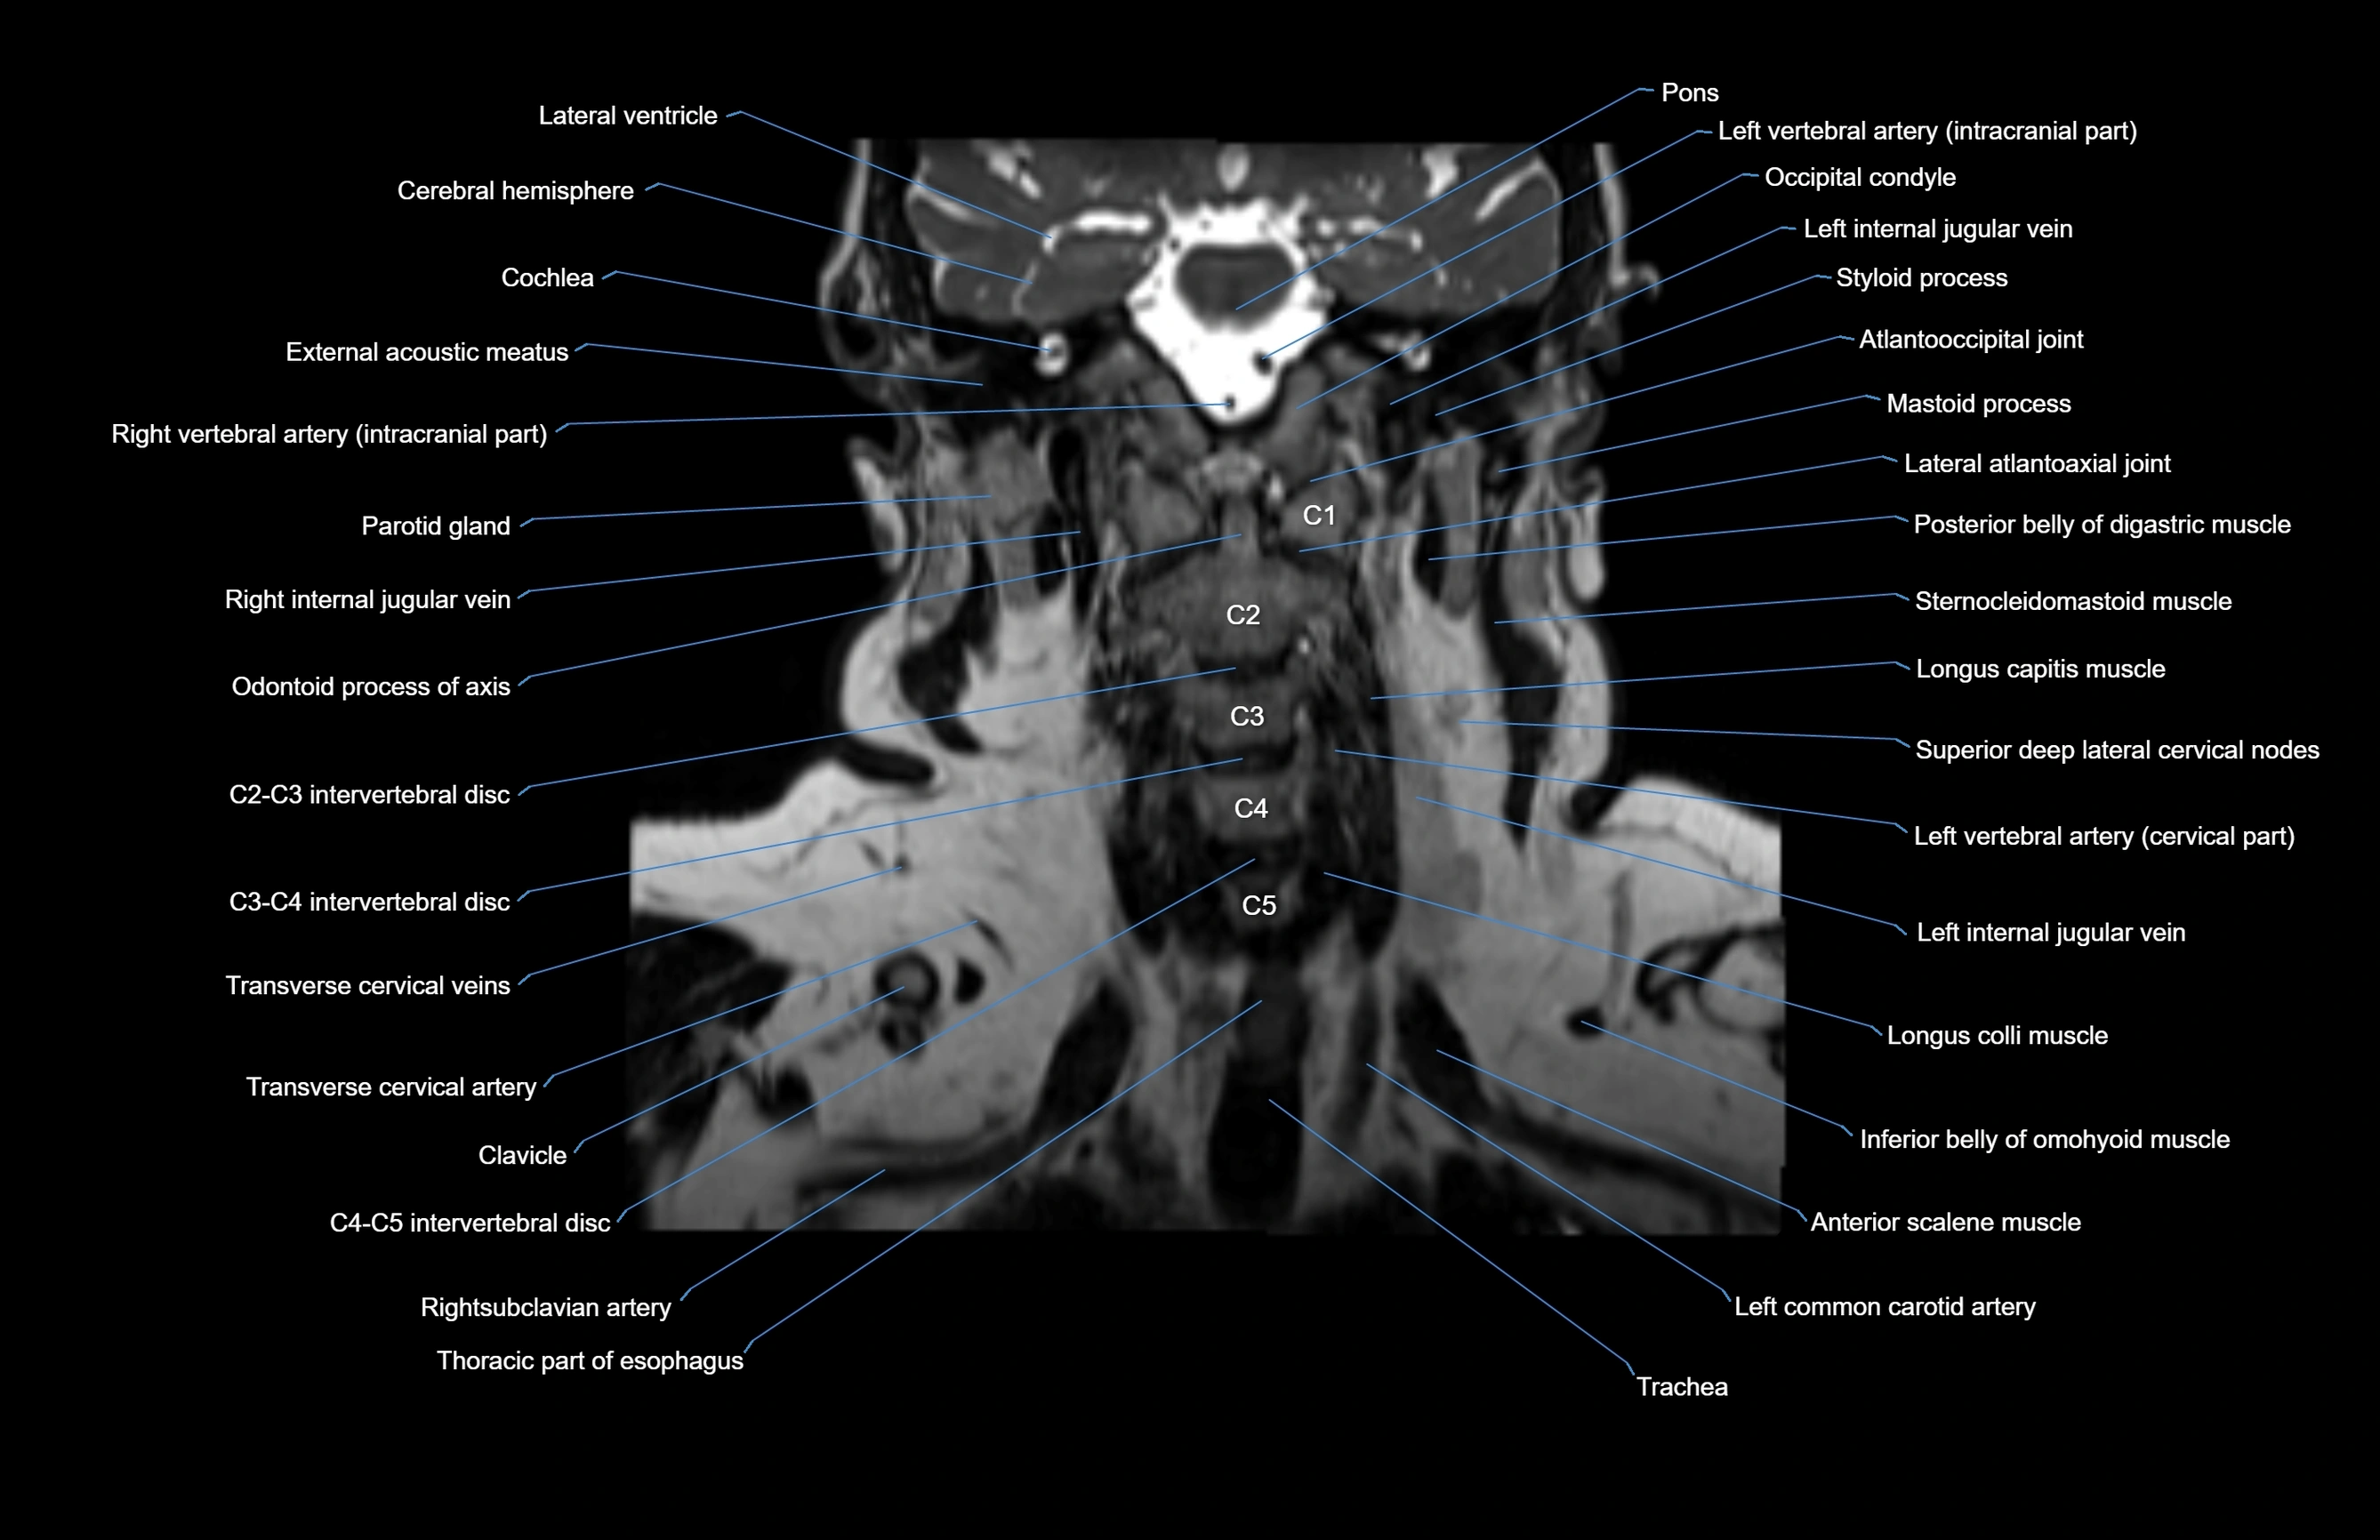

- Occipital condyle

- Lateral atlantoaxial joint

- Longus capitis muscle

- Longus colli muscle

- Inferior belly of omohyoid muscle

- Scalenus anterior muscle (Anterior scalene muscle)

- Left common carotid artery

- Left vertebral artery (cervical part)

- Superior deep cervical lymph nodes

- Transverse cervical artery